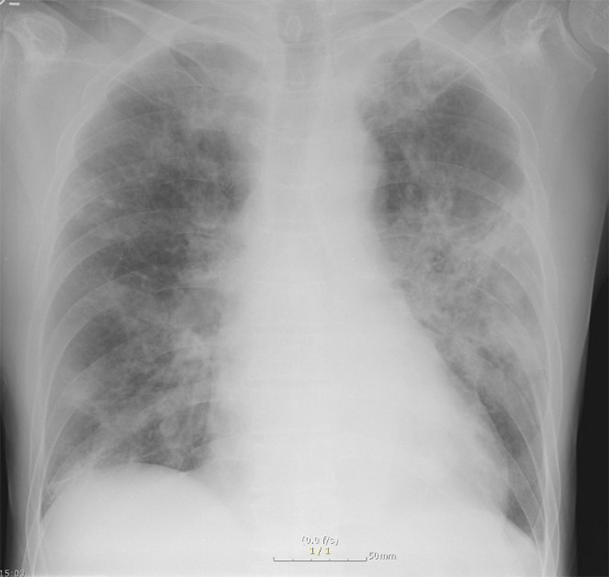

활동성 폐결핵과 비결핵성항산균 폐질환의 진단은 어떻게 하는지요?

환자의 임상 증상 문진과 진찰 후, 흉부 X선 검사 및 흉부 CT가 진단에 도움이 됩니다.

그림: 폐결핵과 비결핵성항산균 폐질환의 흉부엑스레이 사진과 흉부전산화단층활영 사진

비결핵성항산균 폐질환은 폐결핵과 비교하였을 때 서서히 진행하거나 변하지 않을 수 있으며, 만성적인 경과를 보이고, 진단이 늦어지는 경향이 있습니다. 두 질환은 모두 환자의 객담을 통한 객담 항산균 도말검사, 객담 항산균 배양 검사를 진행합니다. 객담 배양이 되기 전에는 객담 도말 검사 양성 소견만으로는 결핵균과 비결핵성항산균이 구별이 되지 않으며, 구별을 위해서 결핵균 핵산증폭검사(TB-PCR) 검사를 시행합니다.